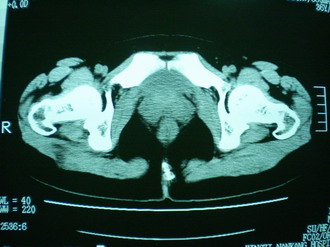

子宫增大,内可见类三角形低密度区,子宫后方可见类圆形团块状影,内部密度不均匀,可见靶样结构,结合病史考虑1子宫后方宫外孕(宫内假孕囊形成)2子宫肌瘤合并妊娠

子宫明显前倾,增大,宫颈增大呈分叶状。子宫直肠窝见不规则形水样低密度。(膀胱胀尿不理想)

考虑:1、宫颈部占位;

2、子宫直肠窝少量积液(盆腔炎所致)。

考虑肌瘤堵塞子宫颈管导致宫腔积液。

考虑:1、宫颈部占位(宫颈癌?);

2、子宫直肠窝少量积液。

1、前曲子宫,2、宫颈部占位?3、盆腔及右输卵管积液?宫内积血?4、左侧卵巢囊肿。